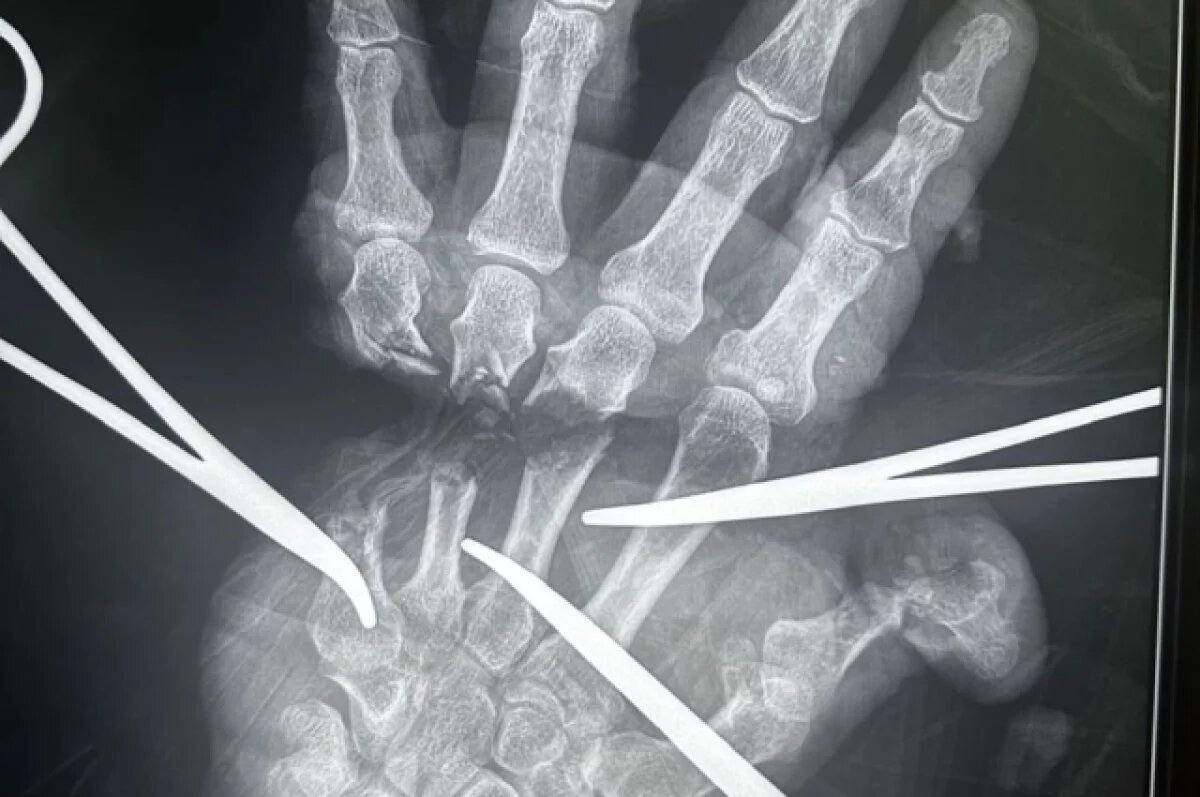

В Новосибирске медики восстановили отрезанную кисть пациента

В Новосибирской области медицинские специалисты Городской клинической больницы № 34 провели успешную реплантацию кисти у мужчины, который получил серьезную травму в результате несчастного случая с электроинструментом. По информации Минздрава региона, операция началась всего через 18 минут после поступления пациента в медицинское учреждение.

В ходе сложной микрохирургической процедуры, которая включает восстановление сосудов, нервов, сухожилий и костей, команда врачей продемонстрировала высокую слаженность действий. В состав группы вошли микрохирурги, травматологи-ортопеды, анестезиологи-реаниматологи и операционные медсестры. Современное оборудование клиники также сыграло ключевую роль в успешном исходе операции.

Главный врач ГКБ № 34 Ярослав Фролов поздравил команду врачей и пожелал пациенту скорейшего восстановления. Он отметил, что операция длилась несколько часов и требовала ювелирной точности, а также поэтапного восстановления поврежденных структур для обеспечения жизнеспособности кисти. Фролов добавил, что пациента ожидает длительный процесс реабилитации, однако главное — рука спасена. Реплантация конечностей является сложным и редким видом хирургического вмешательства, требующим высокой квалификации и применения современных технологий.